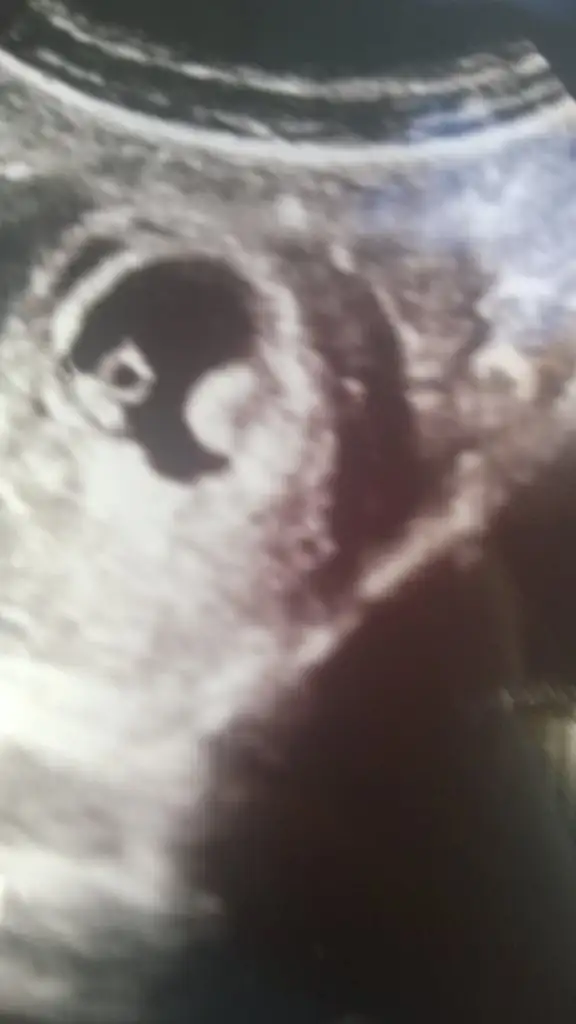

cimcim16 cimcim16 canim doktora gtcektin sonuc ne oldu benimde bebisin yaninda bisi daha var sordum olmasi gereken bi olusum dedi canim

Cnm şimdi geldim şukur iyi herşeyy...benim kesedeki oluşum devam ediyor doktor dedi unut bunu hiç önemli değil...belki ufak bir kanama oldu kaldı orada öyle dedi kılcal damarlarda falan ama umursamadı

benimkide olmasi gereken bi olusum icerde kanama vs yok 1 hafta icindede ii buyumus dedi resjm yukleyemiorum ama gecen haftaya gore bebekte o yanindakide buyumus komsumda bebegin esidir olur dio anlamadm ama kotu olsa derdi heralde

Cnm bu yokk değil dimi...bak bendede böyle birşey var tabi resmi çekme yonune göre değişir benimki kenarda gibi göstererek cekmişti ultrasonu bak yukluyorum...2 haftadır uzuntuden delirdim ama bugunkı dr çok iyi medikalde Ahmet yılmaz güveniyorum ona hiç kafana takma bebeğe zararı olmaz dedi unut onu dedi